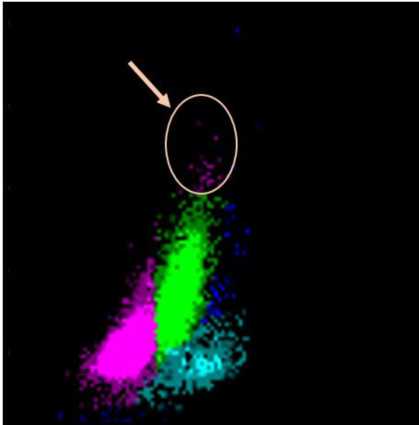

Automated PB count revealed bicytopenia and leukocytosis (hemoglobin: 5.2 g/dL, platelets 75 x 109/L, white blood cells 93.73 x 109/L). Sysmex XE 5000 analyzer reported a flag “blasts?” that was already present in all patient´s CBC since CLL diagnosis. While anemia, leukocytosis and thrombocytopenia could be interpreted as CLL relapse, scattergram cytoDIFF was suspicious for the presence of blasts and required further examination (Figure1).

Fig. 1. Sysmex 5000 – Scattergram cytoDIFF